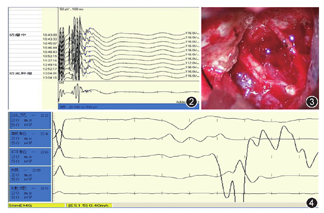

术中及术后面神经诱发电位及其传导均无明显变化(图2),术后肿瘤完全切除且面听神经走行清晰可见;术中诱发肌电图可见刺激面神经后产生动作电位(图3,图4,图5)。术后3 d两组患者的听力下降后组症状差异无统计学意义(P>0.05);但监测组术后麻木症状发生率显著低于非监测组,面神经功能分级表现也较非监测组有显著提高,差异均有统计学意义(P<0.001);同时发现监测组的面神经功能分级仍然显著优于非监测组(χ2=8.225,P=0.004);而术后1个月监测组其预后GOS评分明显高于非监测组,差异均有统计学意义(P<0.001)(表3)。

所有患者均采取经乙状窦后入路法显微镜下切除肿瘤。(1)监测组:患者麻醉后取侧卧位,安装手术头架,描记耳后直形切口,确保骨窗上至横窦下缘,外达乙状窦。由电生理监测医师于皮肤相应部位逐点消毒,刺入电极针(监测范围包括:咬肌、眼轮匝肌、口轮匝肌、颏肌、环甲肌),电生理监测仪(尼高力)可通过体表肌电感应测诱发肌电图、双侧脑干听觉诱发电位、面神经运动、感觉诱发电位及运动诱发电位。待设备连接及确保运行良好后,常规消毒铺巾后,逐步开颅。在电生理监测下确保肿瘤瘤壁无神经分布后,切开瘤壁充分减压,在遇到不确定的条索样结构时实施主动神经电刺激,根据结果决定是否切断。(2)非监测组行常规乙状窦后入路法显微镜下听神经鞘瘤次/全切除术,无术中电生理监测,余手术步骤同监测组相同,在切除听神经鞘瘤时通过显微镜下辨析肿瘤同周围组织的毗邻关系决定行全切或次全切,术后治疗与监测组无异。

本次研究期间共出现3例术中面神经监测失败案例。实施面神经监测的所有患者均未使用肌松药物,因此排除外肌松药物影响[16]。3例患者中有2例为多年高血压及糖尿病,既往血糖控制不佳,且3例患者其术中血压稳定性较差。因此我们认为术中面神经监测成功与否同患者术中血压波动及既往糖尿病病程长短及控制情况紧密相关[17]。多数老年血糖控制不佳的糖尿病患者合并周围神经病变,影响电生理传导[18]。其次肿瘤的大小,病程的长短会导致面听神经受压及损伤的程度有很大差异[19],尤其对于术前有面神经功能障碍(轻中度面瘫)患者,其术中自由肌电描记反应在预设水平处不够敏感,从而造成监测失败。但术中面神经监测具体采用多大的电流刺激可以帮助判断真正的神经损害的相关研究较少。目前为止仅有一项国外研究显示,0.4 mA被认为是中耳手术中面神经刺激的最佳强度[20]。国内患者术中面神经监测采用多大的电流刺激最为合适,有待进一步研究。其他在研究结果评估方面未进行术后2周、术后1个月面神经功能分级的评估,仅是在术后1个月进行预后GOS评分,虽结果显示有显著差异,但未实现一个连续的随访观察。考虑到患者听神经功能恢复是一个漫长的过程,截至数据统计日,我们仅对部分患者(术后3个月以上)听力恢复情况进行了统计,由于数量较少,未进行统计分析,在后续研究中我们将继续跟进,并补充相关评价指标。